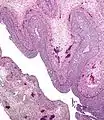

يتشكل الجسم الأصفر من حويصلة مبيضية أثناء الطور الأصفري للدورة الشهرية أو دورة الشهوة ، بعد إطلاق بويضة ثانوية من الحويصلة أثناء الإباضة. تقوم الحويصلة أولاً بتكوين جسم نزفي قبل أن يصبح الجسم الأصفر ، لكن المصطلح يشير إلى المجموعة المرئية من الدم ، التي تُترك بعد تمزق الحويصلة ، التي تفرز البروجسترون. في حين أن البويضة (في وقت لاحق الزيجوت إذا حدث التخصيب) تخترق قناة فالوب إلى الرحم ، يبقى الجسم الأصفر في المبيض. عادة ما يكون الجسم الأصفر كبيرا جدا بالنسبة لحجم المبيض. في البشر ، يتراوح قطره من أقل من 2 سم إلى 5 سم. [4]

تنمو خلاياه من الخلايا الجريبية المحيطة بالحويصلة. [5] يتم توليف البروجسترون من الكوليسترول بواسطة كل من الخلايا الأصفرية الكبيرة والصغيرة عند النضج المرحلة. مجمعات الكولسترول - LDL ترتبط بالمستقبلات على غشاء البلازما من خلايا الجسم ومحمية. يتم تحرير الكولسترول وتخزينه داخل الخلية على شكل استر كولسترول. يتم إعادة تدوير LDL لمزيد من نقل الكوليسترول. تنتج خلايا الأصفير الكبيرة المزيد من البروجسترون بسبب المستويات غير المستقرة / القاعدية لنشاط البروتين كيناز A (PKA) داخل الخلية. تحتوي خلايا الجسم الأصفري الصغيرة على مستقبلات الهرمون المصفر التي تنظم نشاط PKA داخل الخلية. PKA يقوم بفسفرة البروتين التنظيمي الحاد الستيرويد (ستار) وبروتين ناقل لنقل الكولسترول من الغشاء الميتوكوندريا الخارجي إلى غشاء الميتوكوندريا الداخلية. [6]

ويصاحب تطور الجسم الأصفر زيادة في مستوى إنزيم ستيرويدوجينيك سيتوكروم ب450(P450scc) الذي يحول الكولسترول إلى بروتينولون في الميتوكوندريا. [7] ثم يتم تحويل برجنينلون إلى البروجسترون الذي يتم إفرازه من الخلية وإلى مجرى الدم. خلال دورة الإستروجين البقري ، تزداد مستويات البلازما من البروجسترون بشكل موازٍ لمستوي سيتوكروم ب450 و adrenodoxin المانحة للإلكترون ، مما يشير إلى أن إفراز البروجسترون هو نتيجة للتعبير المعزز لـ سيتوكروم ب450 في الجسم الأصفر. [7]

مبيض إنساني مع جسم أصفر كامل النمو